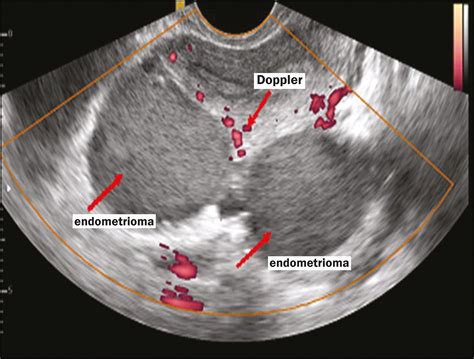

When performing ultrasounds for PCOS, radiologists and gynecologists are not just looking for the presence of follicles. They are evaluating the overall morphology of the ovaries. A healthy ovary typically contains a few developing follicles of varying sizes. In a PCOS-affected ovary, the imaging often reveals a "string of pearls" pattern—a ring of small, underdeveloped follicles located around the periphery of the ovary.